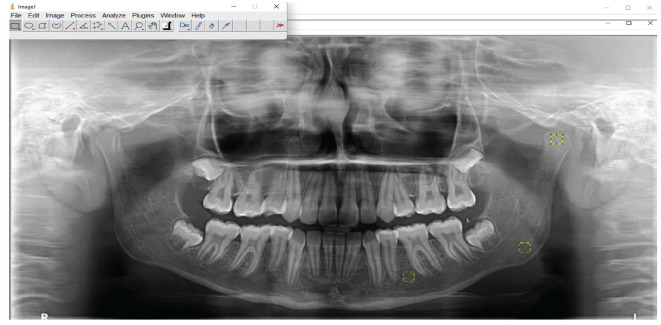

Objective: The aim of this retrospective study was to compare the effects of the Twin block and Herbst appliances on the mandibular trabecular pattern using fractal dimension analysis (FDA) of panoramic radiographs (PRs).

Methods: The PRs of 50 subjects with skeletal Class II malocclusion who underwent the Twin block (T-group, average age: 11.63±0.87; 25 girls, 25 boys), 50 subjects with skeletal Class II malocclusion who underwent the Herbst (H-group, average age: 11.72±0.91; 27 girls, 23 boys), and 50 controls (C-group average age: 11.67±0.83; 24 girls, 26 boys) were selected. The condyle, corpus, and angulus regions of all groups in the mandible were examined using FDA.

Results: The condylar region (p≤0.001) and corpus mandible in the treatment groups (T-group: right, p≤0.05, left, p≤0.01; H-group: p≤0.05), as well as the left and right condylar region (p≤0.001) and left corpus mandible (p≤0.05) in the C-group, all indicated substantial increases in FDA between T0 and T1. Inter-group comparisons indicated that the T-group had greater variances in the condyle (p≤0.001) compared to the H group.

Conclusion: As the findings revealed both Twin block and Herbst appliances not only contributed to the dentoalveolar structure but also provided remodeling of the mandibular trabecular structure. Consequently, the null hypothesis was rejected.